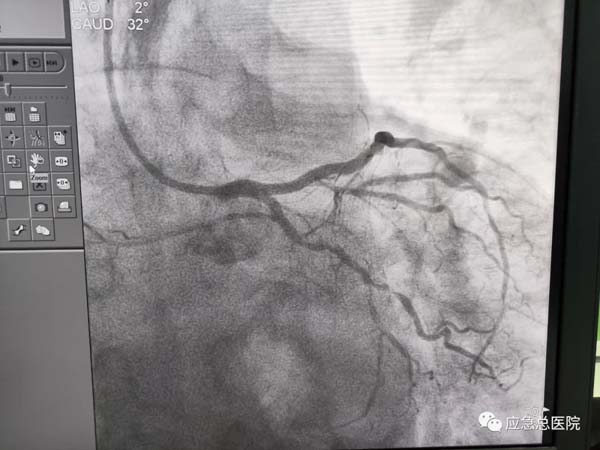

手术后

生命在接力。来到应急总医院后,为患者第一时间进行造影检查,结果提示:三支病变,前降支近端100%闭塞,也就是说供应心脏的三条血管均有严重的狭窄,而最主要的血管——前降支已经完全堵死,晚一点救治后果不堪设想。吴迪教授第一时间研判:务必马上开通闭塞血管,一刻都不能耽搁!因为应急总医院有一支经验丰富的介入团队,在吴迪教授的指导下,在范煜东副主任的熟练操作下,在张子龙副主任医师、张庆军主治医师及导管室护士、技师的通力配合下,病人的闭塞血管及时开通,如久旱甘霖般将鲜活的血液重新给濒临坏死的心肌细胞。手术一做完,病人就长舒一口气:“不疼了!舒服了!”在手术室门口焦急守候的家属,此刻喜极而泣。看看时间,从张大爷到光熙医院就诊,再转运到应急医院完成手术,仅用了50分钟。